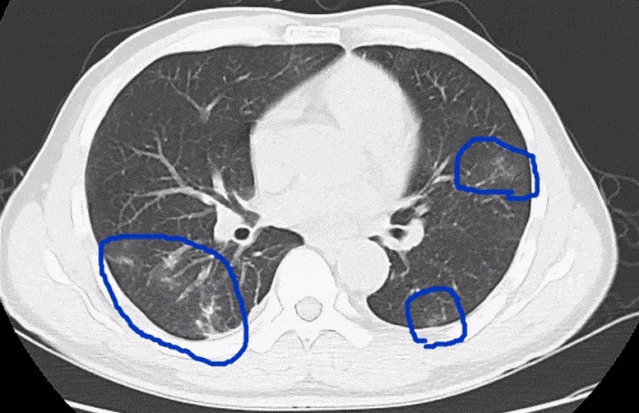

2020年9月,深圳的一家三口在品尝“醉蟹”后,先后出现发热、腹痛、腹胀、乏力、食欲下降、干咳等症状。经检查,他们均患上了“肺吸虫病”。

△图源:深圳卫健委